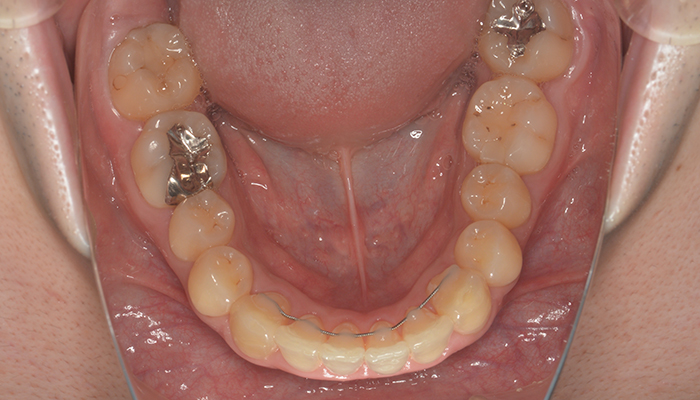

実際の患者様のお口の状況を知るために、口腔内写真、顔面写真、レントゲン撮影、上下顎模型印象、噛み合わせ確認、歯周病検査、デジタル印象などを行なっていきます。4番の抜歯(1本)

上の片側4番目の歯を1本抜歯しました。その他の健康な歯は抜歯していません。(親知らずは抜歯しています)

ワイヤーだと片側抜歯を行うと正中のラインが抜歯した方向へ流れてしまうことがありますが、今回はマウスピース型矯正装置(インビザライン)で行ったため、そのような反作用は生じませんでした。

抜歯した場合でも治療期間はワイヤーに比べ予定より3ケ月も治療期間を短縮できました。しっかりと定期的なチェックとメンテナンスにも通っていただけたお陰です。